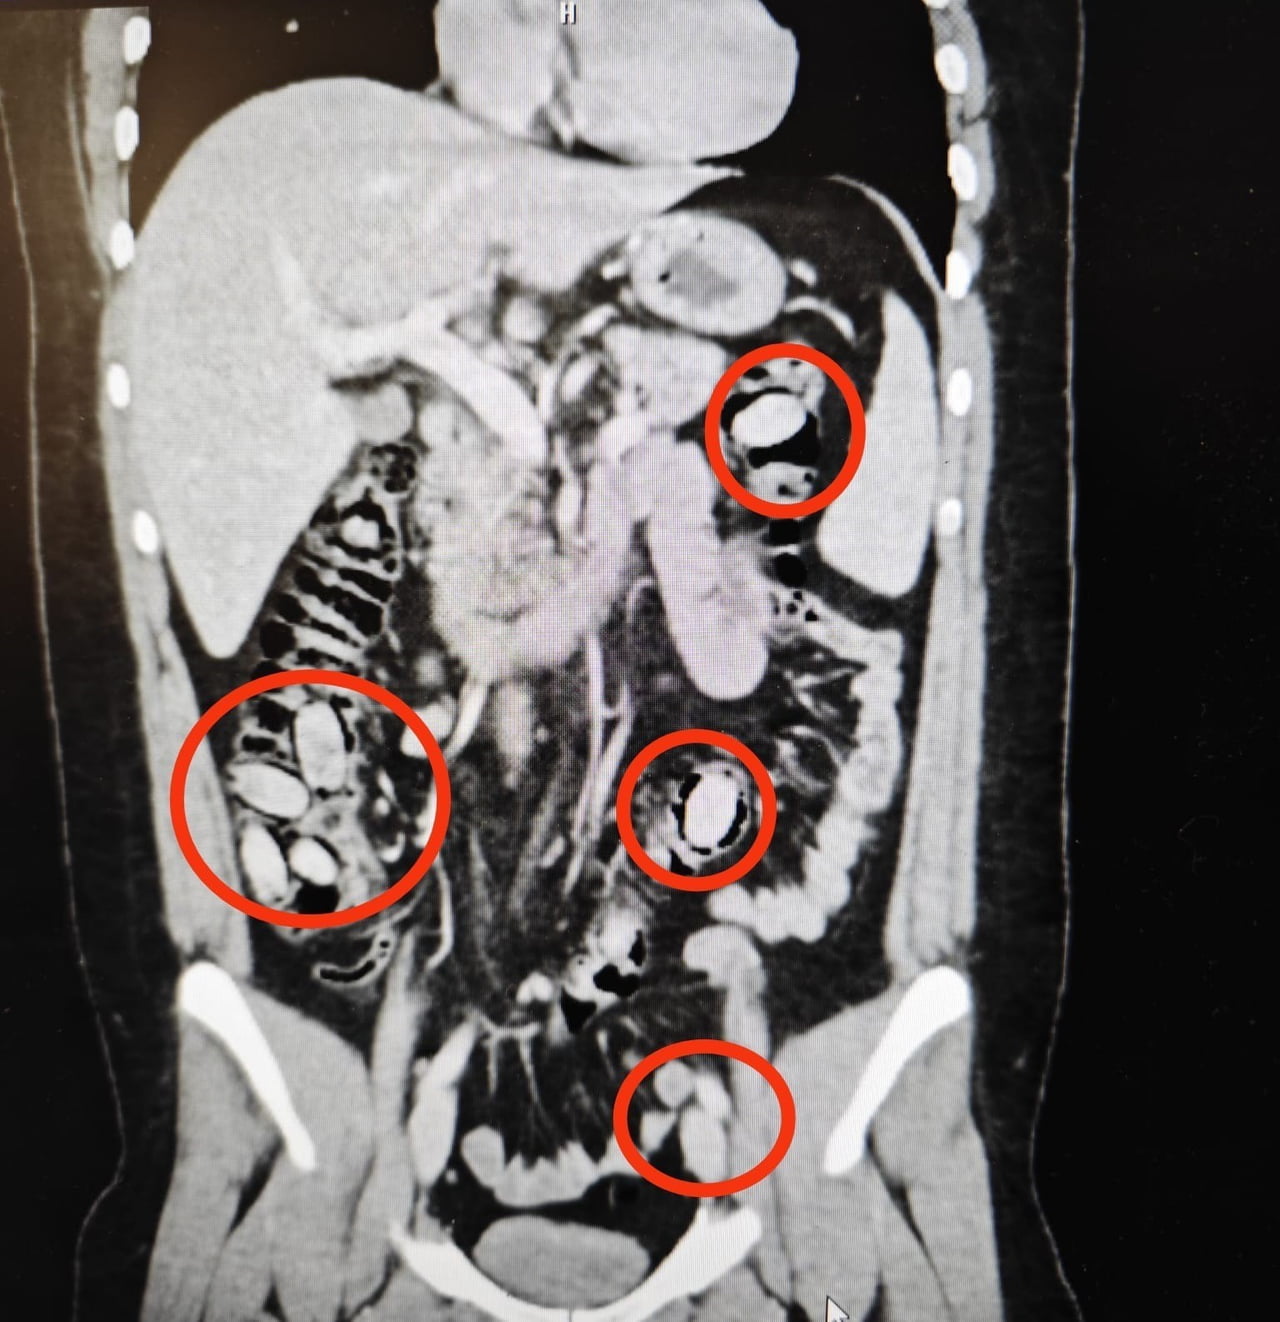

Kent girişindeki bir kontrol noktasında durumundan şüphelenilen şahıs, hastanede yapılan detaylı tetkikler sonucunda midesinde metamfetamin kapsülleri taşıdığı belirlendi.

Yapılan cerrahi müdahale ile 44 kapsül uyuşturucu madde midesinden çıkarılan S.A., tedavisinin ardından mahkemeye sevk edildi ve tutuklandı.